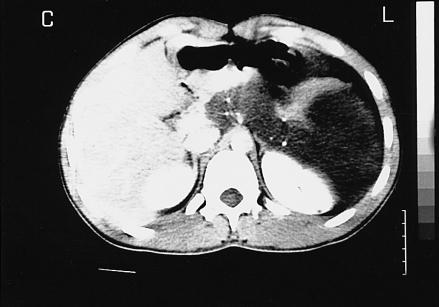

Retroperitoneal cystic lymphangioma is a rare congenital malformation. The majority of lymphangiomas are present at birth and nearly all present before the age of two years. We report a case of giant cystic retroperitoneal lymphangioma in a patient who first presented with symptoms at the age of 7, underwent surgery, and who then suffered a recurrent mass 11 years later.

腹膜后囊性淋巴管瘤是一种罕见的先天性畸形。大多数淋巴管瘤在出生时就存在,几乎所有病例在两岁前出现。我们报告一例巨大腹膜后囊性淋巴管瘤病例,该患者首次出现症状是在7岁,接受了手术,11年后出现复发性肿块。